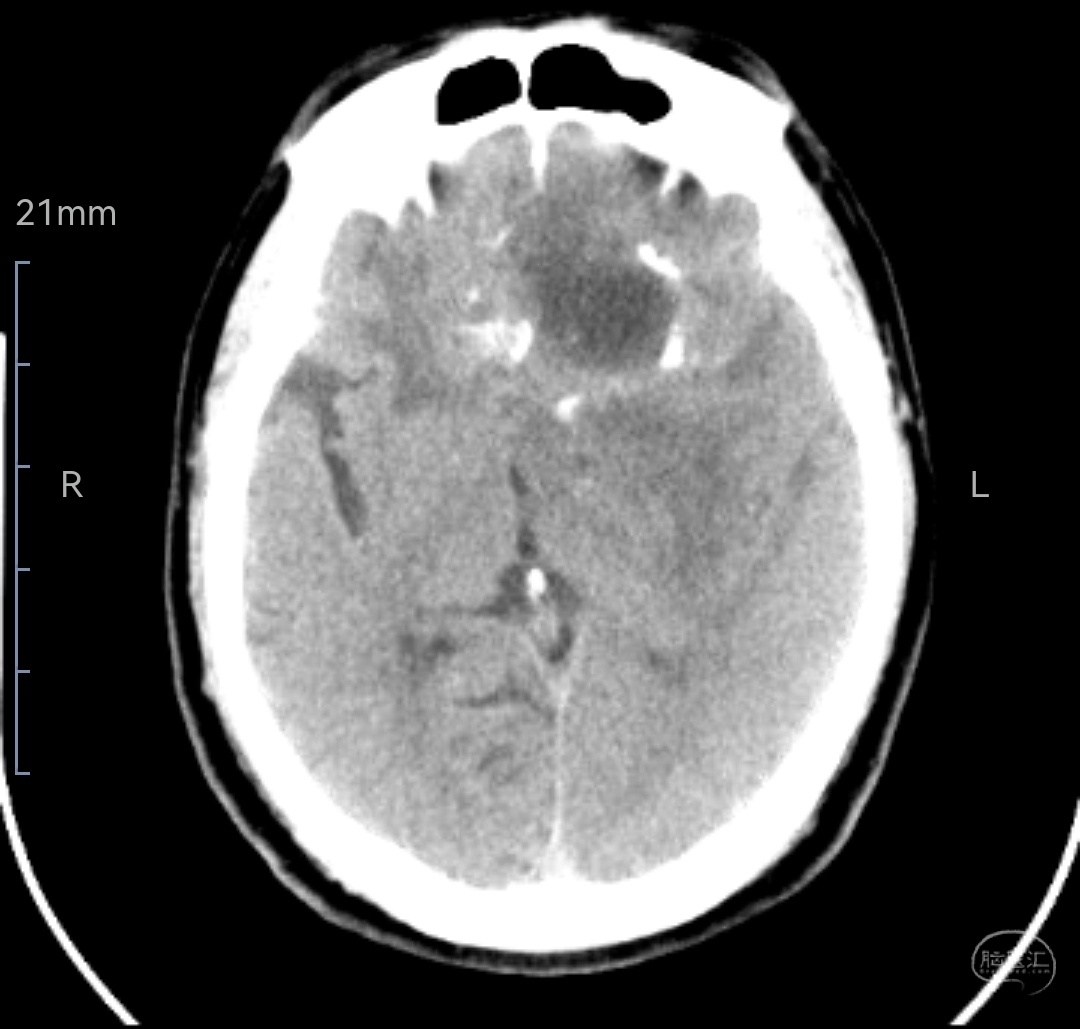

CT示肿瘤混杂密度,伴有局部钙化及囊变

在影像学上,CT和MRI显示胶质肉瘤为不规则肿块,外壁光滑,与周围脑实质界限清楚,周围水肿明显。此外,胶质肉瘤更常发生于颞叶,在大体形态上与脑膜瘤相似。Han等发现,胶质肉瘤一般为较大病变,在T1加权图像上呈低信号,在T2加权图像上呈高信号,表现为坏死和中央钙化区(以不均一增强为特征),周围或不规则强化和中线结构移位。MRS则显示胆碱(Cho)波峰,正常的肌酐(Cr)和低的乙酰天冬氨酸(NAA)。